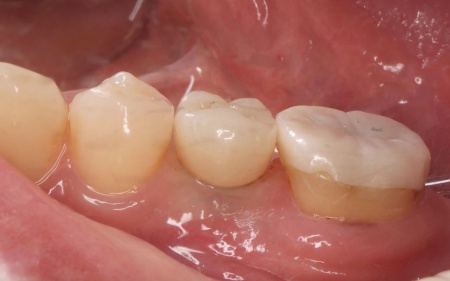

治療前

治療中

治療後

| 行ったご提案・治療内容 | 診断結果をお伝えし、患者様の了承を得たうえで左下奥歯の被せ物を外したところ、レントゲン検査での診断どおり、歯根が割れていることが確認できました。 そのため、患者様には左上下奥歯とも温存が難しい旨を説明し、抜歯に同意いただきました。 患者様は、以前当院で人工歯根を顎の骨に埋入して歯を装着するインプラント治療を受けていたため、今回も左上下奥歯ともインプラント治療を希望されています。 メリット デメリット 改めてメリットとデメリットをしっかりお伝えしたところ、インプラント治療に対する不安はないとのことで、治療に同意いただきました。 まず、左上下奥歯を慎重に抜きます。 インプラント手術後は経過観察を行い、インプラントが顎の骨に結合したことを確認したら、インプラント上部に取り付ける人工歯を作製するために精密な型取りを実施します。 後日、完成した人工歯をインプラントに装着し、使用感や見た目に問題がないことを確認して、治療を終了しました。 |